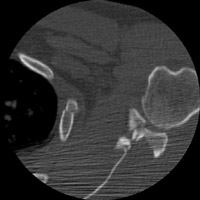

- Click on the image for a larger versionBAxial CT. This image is acquired through the shoulder and shows a comminuted fracture of the glenoid as well as one of the rib fractures identified in the chest radiograph.